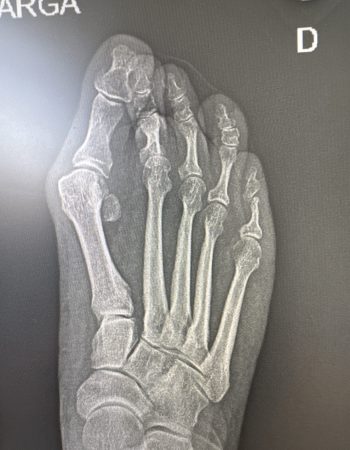

Os presento un caso de deformidad de hallux valgus intervenido con una técnica de cirugía percutánea de 3ª generación. En este ocasión, se ha realizado unas osteotomías en el primer metatarsiano y en la primera falange que se han fijado con tornillos que confiere a la corrección estabilidad, seguridad y menor dolor postoperatorio manteniendo el respeto a las partes blandas.

Los resultados radiográficos y clínicos los podéis ver en las fotos antes de la cirugía y los 3 meses de la misma.